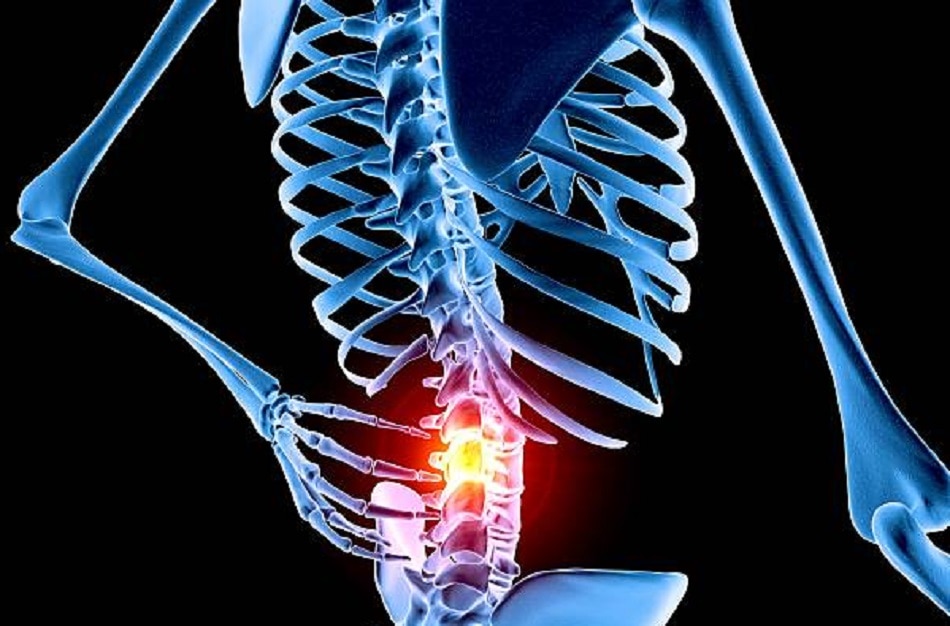

क्या है एवैस्क्लुर नेक्रोसिस- एवैस्क्लुर नेक्रोसिस (AVN) में शरीर के किसी भाग में हड्डियों तक खून की सप्लाई बंद होने से उन पर बुरा असर पड़ने लगता है. इस तरह हड्डियों के टिशू गलना शुरू कर देते हैं और धीरे-धीरे हड्डियां गलना शुरू हो जाती हैं. इसमें हड्डियां को हाल ठीक वैसे ही होता है जैसा ब्लड सप्लाई बंद होने के बाद दिल और दिमाग का होता है. जब दिल तक ब्लड सप्लाई नहीं होती तो इंसान को हार्ट अटैक आता है और दिमाग तक सप्लाई बंद होने से स्ट्रोक की दिक्कत होती है.

Photo Credit: Getty Images

क्या हैं लक्षण- AVN के मरीजों में कई तरह के सामान्य लक्षण देखे जा सकते हैं. उन्हें कूल्हे और कमर में दर्द की समस्या हो सकती है. खड़े होने या चलने में भी परेशानी हो सकती है. जोड़ों में बहुत दर्द रहने लगता है. इसलिए शरीर में इस तरह के लक्षणों को बारीकी से देखें और समय पर जांच जरूर कराएं.